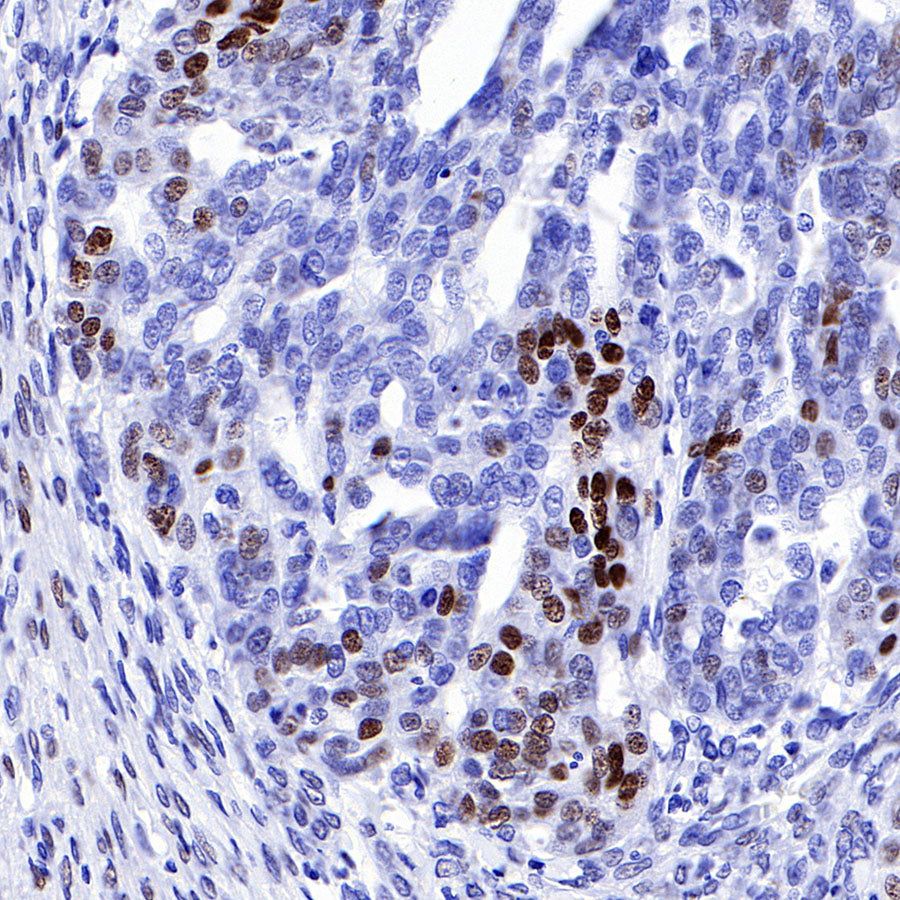

IHC shows positive staining in paraffin-embedded human endometrial cancer. Anti-Progesterone Receptor antibody was used at 1/500 dilution, followed by a HRP Polymer for Mouse & Rabbit IgG (ready to use). Counterstained with hematoxylin. Heat mediated antigen retrieval with Tris/EDTA buffer pH9.0 was performed before commencing with IHC staining protocol.

IHC shows positive staining in paraffin-embedded human ovarian cancer. Anti-Progesterone Receptor antibody was used at 1/500 dilution, followed by a HRP Polymer for Mouse & Rabbit IgG (ready to use). Counterstained with hematoxylin. Heat mediated antigen retrieval with Tris/EDTA buffer pH9.0 was performed before commencing with IHC staining protocol.